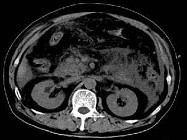

- 单项选择题根据所提供的图像,最可能的诊断是 ( )

A、胰腺癌

B、急性胰腺炎

C、慢性胰腺炎

D、正常胰腺

E、以上都不是